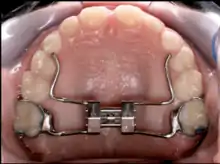

Palatal expansion can be achieved using either fixed or removable appliances.[16]